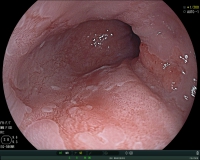

Few patients with heartburn have changes in the esophagus associated with an increased risk of developing adenocarcinoma (esophageal cancer). In these patients, there is a replacement of the normal mucosa of the esophagus with a special mucosa (Barrett's mucosa). In this situation, a specific endoscopic examination is necessary. Hereby, the risk for cancer development can be assessed more accurately and potential precancerous lesions can be treated.

Visualization of a Barrett's mucosa during gastroscopy (view of the lower esophageal portion).